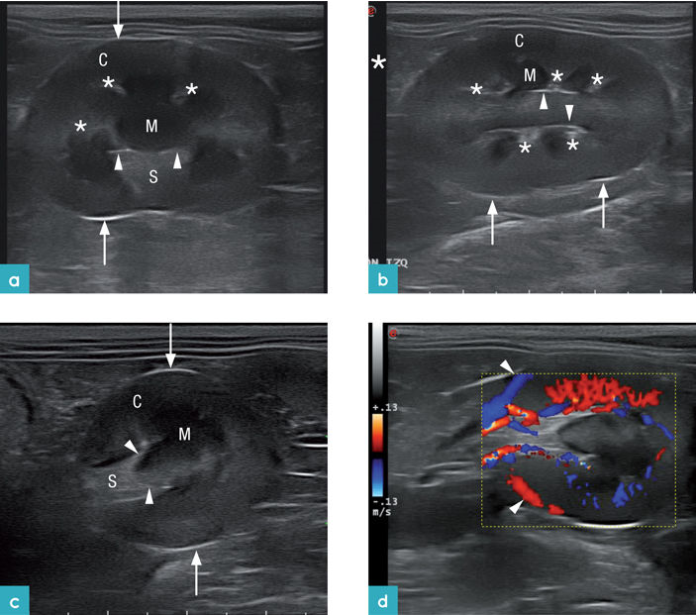

超声波清楚地区分了低回声的肾髓质和皮质的回声波,由于肥胖猫的皮质的脂肪浸润,所以其回声会增强。在健康猫中,由于近端小管的脂肪增加(以液泡的形式),尤其是公猫,所以肾皮质回声会增加。

髓质边缘呈现高回声线,即使在健康猫(没有症状提示存在肾脏疾病)中也可能观察

骨盆凹陷将髓腔分隔,其旁运行小叶间血管。由于肾盂上存在脂肪以及纤维组织,所以肾盂呈现高回声带,并偶尔会出现声影,宽度约为1-2 mm。肾顶部是肾髓质的延伸,并连接着肾盂。肾顶部被肾窦所围绕,而肾窦含有脂肪组织,因此为高回声带,且这一特点在肥胖的猫尤其显著。。使用高频探头可以在肾门处看到肾静脉,但是由于动脉太小很难观察到动脉。肾被膜在肾脏的最外围的区域显示为高回声线 (图4.视频 1)。健康动物的肾脏是没有液体围绕的。